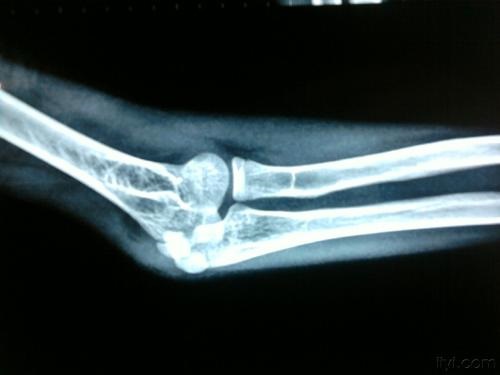

肘关节脱位图

肘关节脱位是临床上骨折后的一种常见状况,发病时有韧带、骨关节及肌肉组织损伤等伴随着出现。